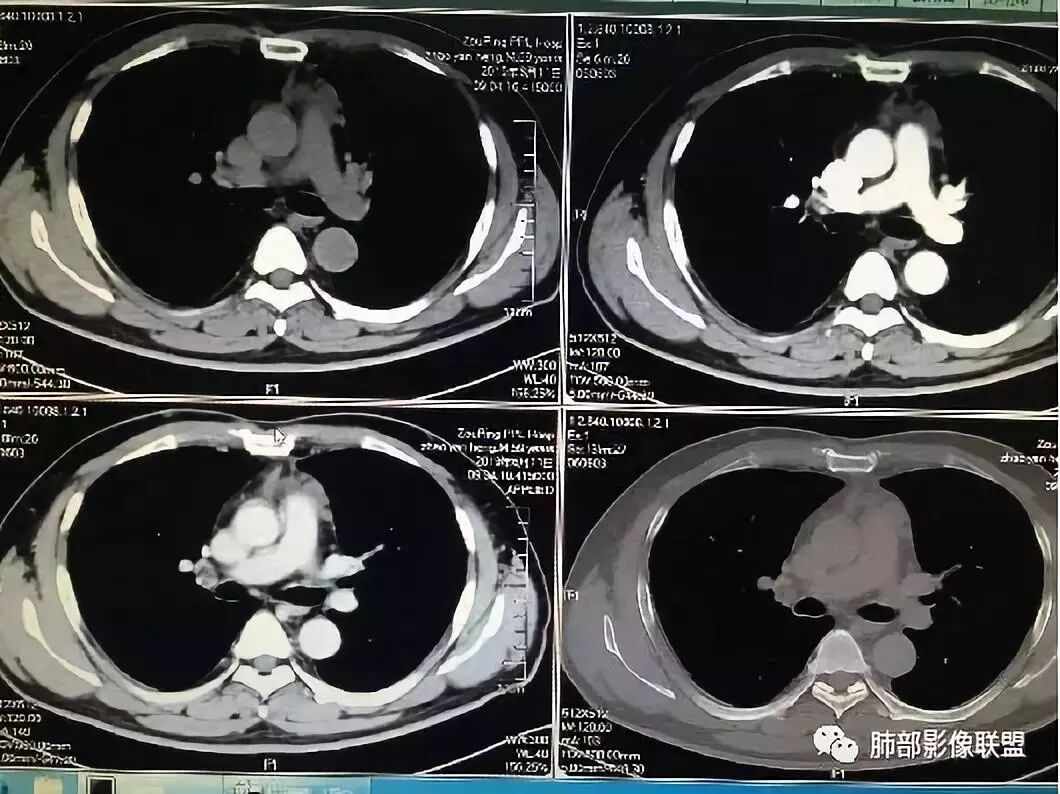

胸腺区小高密度灶,梭形

边缘张力不高

因为原病灶没看到,现在原有位置有一大病灶,如果是新发的,原有病灶会推移一边,但是没看到,倾向于原病灶增大

根据强化,高的70HU,低的没测,考虑囊实性

实性部分明显强

偏一侧

上面来的血供,病灶深分叶

附近心包似乎也不干净

有淋巴结